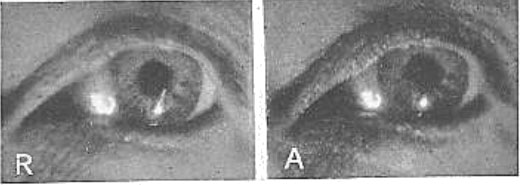

Рис. 26. Изображение электрической нити накала на передней поверхности хрусталика

R, состояние покоя; А, аккомодация. Под увеличительным стеклом никакого изменения размера двух изображений не наблюдается. Изображение справа выглядит больше только потому, что оно более четкое. Для поддержания теории Гельмгольца оно должно быть меньше. Хвостик кометы на рисунке слева – это случайное отражение от роговицы. Отблеск света внизу – просто отражение вспышки фотокамеры, на которую был запечатлен глаз. Потребовалось два года, для того чтобы получить эти фотографии.

R, состояние покоя; А, аккомодация. Размеры изображений на обеих картинках одинаковые. Изображение на роговице настолько мало́, что оно не претерпело заметных изменений при несильном изменении, которое имело место в роговице во время аккомодации. На рисунке А оба изображения изменили свое расположение, а замыкающая часть отражения от хрусталика была отрезана радужкой, но она остается той же самой. Белый блик между двумя изображениями нити накала есть отражение от лампы, использовавшейся для освещения глаза. Заметьте, что на рисунке А видна бо́льшая часть склеры, что указывает на удлинение глазного яблока во время аккомодации.